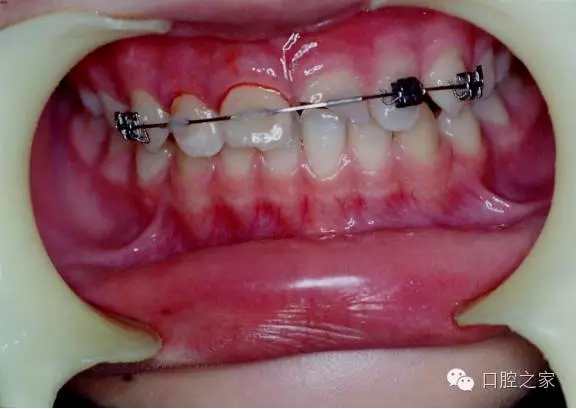

兒童外傷牙常用固定方法

一、結(jié)扎絲結(jié)扎法

二、主鋼絲(夾扳)+結(jié)扎絲結(jié)扎法

三、鋼絲(主鋼絲或結(jié)扎絲)+樹(shù)脂夾扳固定法

四、塑料基托式固定法(全牙列合墊)

五、托槽輔助固定法